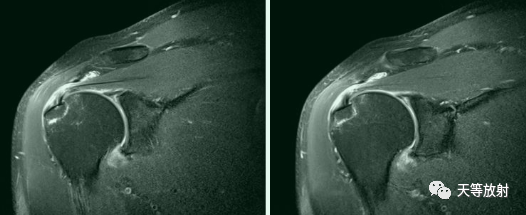

Bankart损伤的MR表现

三角形变钝

盂唇撕裂:关节盂唇软骨与盂缘可见线状高信号影并连续到关节面下

盂唇完全消失或盂唇明显移位

若盂唇损伤合并关节盂骨质损伤,称为骨性Bankart病变